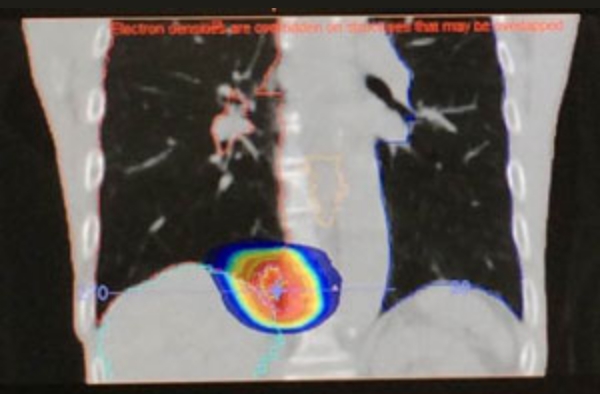

腹部リンパ節転移

他院からのご紹介例

呼吸性移動の管理

治療前の毎回の動画撮影

実際は腫瘍も肺全体も呼吸とともに上下左右に動いています。腫瘍(白い点)が照射野内であることを毎回確認して実施